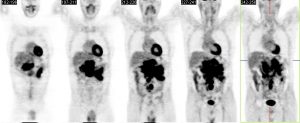

Examen initial: Volumineux ganglions hypermétaboliques mésentériques.

Evaluation de la réponse thérapeutique: Disparition des ganglions hypemétaboliques, réponse métabolique complète, score de Deauville 1

Apparition des multiples foyers hypermétaboliques hépatiques, très ponctuels.

Candidose hépatique chez un patient immunodéprimé